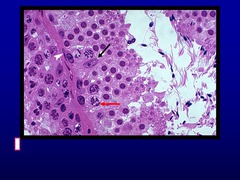

Ballooning Degeneration, Papular Stomatitis Arrows= inclusion bodies

describe this oral mucosa. What is the arrow? disease?